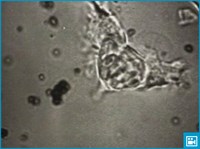

Лимфа — прозрачная, слегка желтоватая жидкость, содержащая значительное количество лимфоцитов. Она содержится в лимфатическом русле, которое присутствует в большинстве органов и тканей человеческого организма. Русло начинается слепыми лимфатическими капиллярами, в которые поступает жидкость из тканей. Из лимфатических капилляров лимфа попадает в более крупные лимфатические сосуды, которые образуют большие лимфатические сети и сплетения.